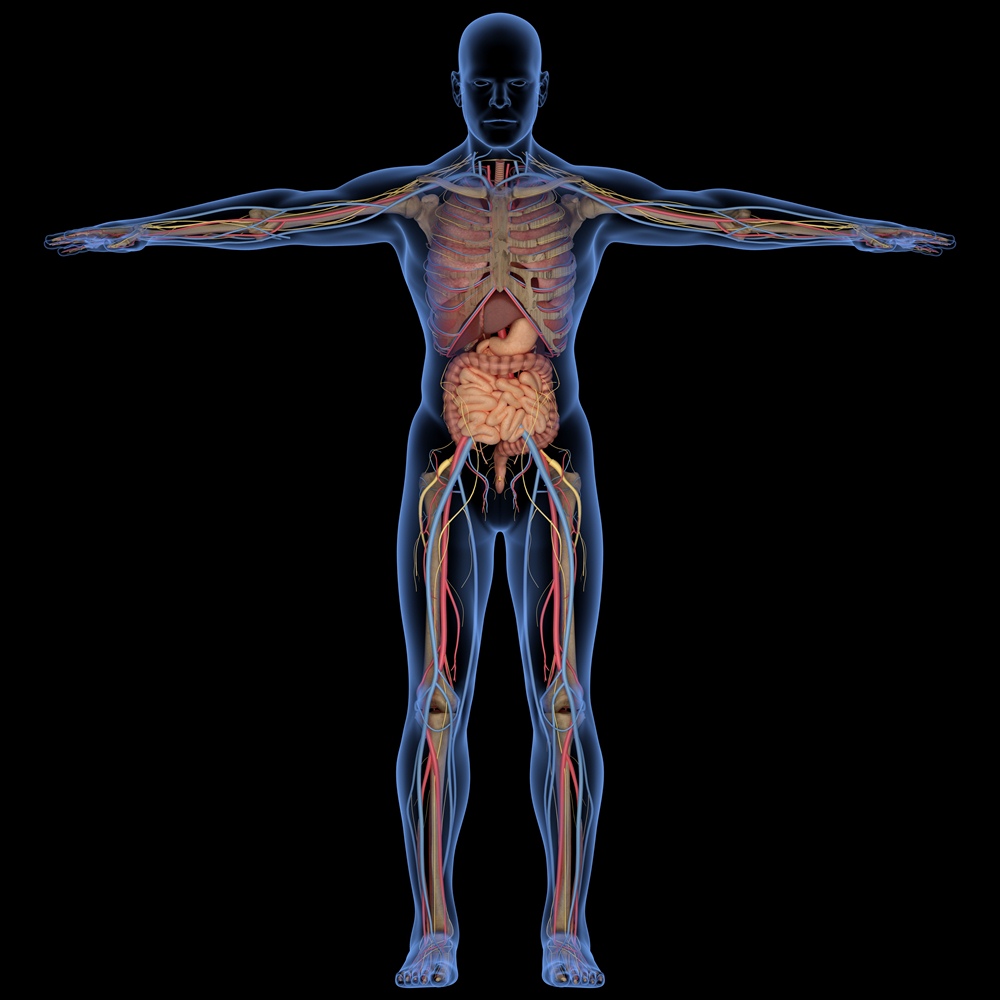

I qualified at the London Foot Hospital. My work is to biomechanically assess positions of joints, of the feet, ankles, knees and hips in relation to find the best positions to stand, walk and move, for each individual person. Every person is different and will compensate within joints differently, for the movements, activities, occupations and forces we place upon our bodies.

Foot podiatry biomechanics involves stopping the feet rolling in or out using bespoke foot orthotics.

Bespoke orthotics correct body alignment and improve shock absorption.

Orthotics are used in the treatment of many body problems such as foot problems like, in rolling feet, (pronation) which is often connected with other pain symptoms such as ankle injuries, knee pains, hip conditions and back pains.

In the assessment I examine the feet in a Podiatrists Biomechancial Assessment, in standing, sitting and non weight bearing positions. I assess the alignment and how the pressure is transferred into the feet, for each leg, into the ankles, knees, hips and back.

The foot orthotics I make are made from scanning or taking plaster molds of each foot to capture the exact shape and fit and are accurate to each foot, ensuring the correct angle and maximum shock absorption.

This involves stopping the feet inrolling or out rolling using bespoke foot orthotics. Bespoke orthotics correct body alignment and improve shock absorption

Moulded Orthotics are used in the treatment of many body problems such as, foot problems like, in rolling feet, (pronation) and higher connected problems like, ankle injuries, knee pains, hip conditions

and back pain or injury.

A biomechanical assessment involves assessing both standing, sitting and non weight bearing positions of the joints, in relation to alignment and how pressure is transferred into and through the feet, ankles,

knees, hips and back.

In a consultation I assess both standing, walking, sitting and non weight bearing positions of joints, to find where support is needed.